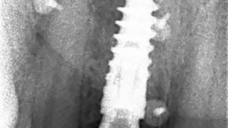

The main issue involved the upper right central incisor (tooth 1.1), which was devitalized and presented recurrent abscesses. Clinical and radiographic evaluation confirmed the presence of buccal bone wall resorption, leading to a significant defect in the alveolar ridge. This condition compromised both the hard tissue and the surrounding soft tissue, posing a challenge for achieving long-term stability and esthetic success in the anterior maxilla.

The patient underwent a thorough risk assessment to evaluate systemic, local, and esthetic considerations. As she had no systemic diseases and maintained good oral hygiene, the overall medical risk was low. Locally, the main risk factors included the compromised buccal bone wall, the presence of infection, and the esthetic sensitivity of the anterior maxilla. These conditions required careful planning to ensure that both hard and soft tissues could be regenerated and stabilized around the implant.